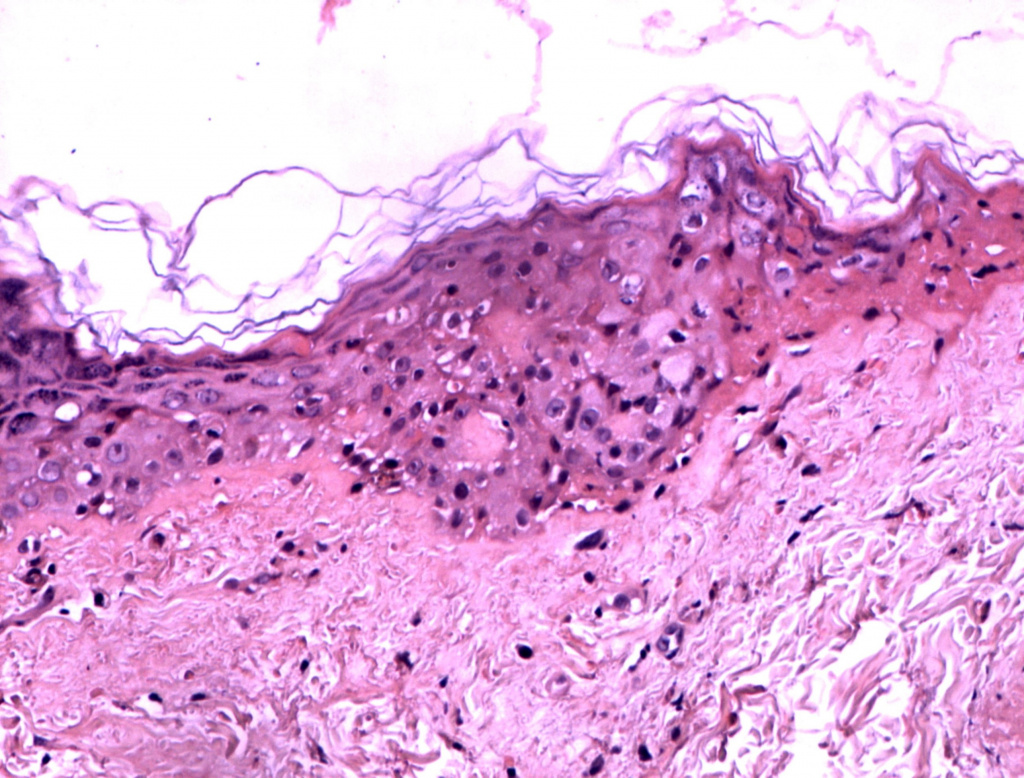

Уже после первой процедуры отмечается выравнивание цвета лица и увеличение тургора кожи (рис. 1-2). Процедуры переносятся очень комфортно, небольшая гиперемия в некоторых случаях держится до 30 минут. По результатам 3D-сканирования уменьшилась выраженность мелких морщин вокруг глаз уже через 6 дней после первой процедуры (рис. 1-6). Также проведено гистологическое исследование сразу после процедуры (рис. 7) (фрагмент «тонкой» кожи: единичными лейкоцитами в толще эпидермиса и на его поверхности, ядра клеток эпидермиса и их цитоплазма на данном участке набухшие, сосочки дермы несколько сглажены, рыхлая волокнистая соединительная ткань сосочкового слоя дермы отечна), на третий день (рис. 8) (отмечается уменьшение количества набухших ядер в эпидермисе, мелкоочаговое кровоизлияние в сетчатом слое дермы с перифокальной сосудистой реакцией и слабовыраженным отеком сетчатого слоя дермы) и спустя 20 дней после процедуры (рис. 9) (В представленном фрагменте кожи заметна умеренная пролиферация клеток эпидермиса и дермы. Отмечается уплотнение коллагеновых волокон сетчатой дермы. Патологических изменений в эпидермисе, дерме, придатках кожи не обнаружено). Также наблюдаются изменения показателей влажности, пигментации и эластичности кожи (рис. 10-11).

Гистология через 20 дней после процедуры HELEO4

Рис. 9. Гистология через 20 дней после процедуры HELEO4™